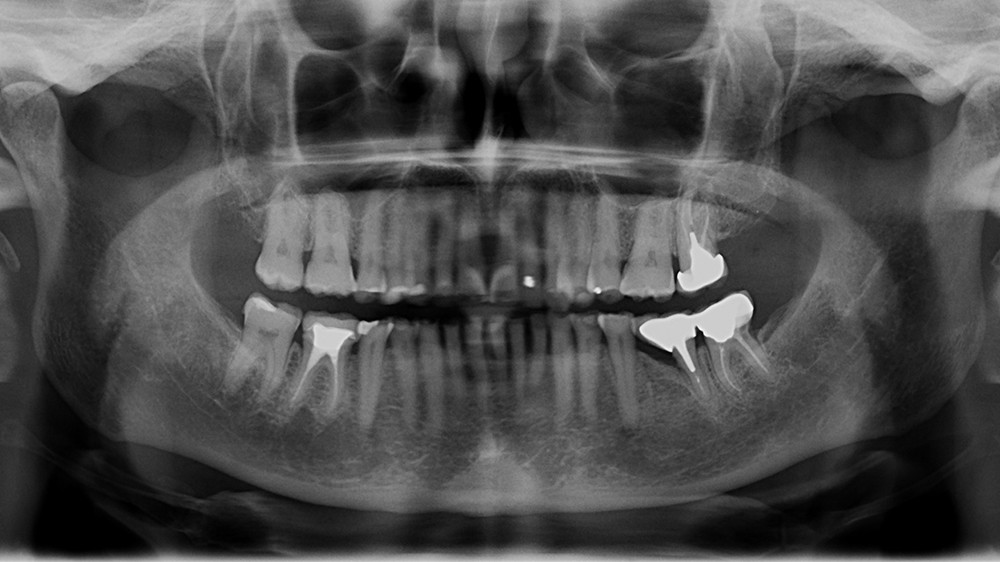

Enfin, une analyse attentive des courbes d’occlusion est menée, notamment dans les cas d’édentements non compensés ou lorsque des restaurations en céramique sont déjà présentes [12] (fig. 1). En effet, la présence de ces dernières peut entraîner une usure différenciée de la dent naturelle antagoniste.

Ainsi, les usures engendrent, dans la majorité des cas, des perturbations au niveau des courbes d’occlusion, lesquelles devront être corrigées lors de la réalisation du wax-up [13].